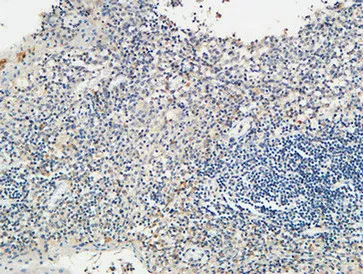

CD68 Rabbit Polyclonal Antibody

Cat: APRab08436